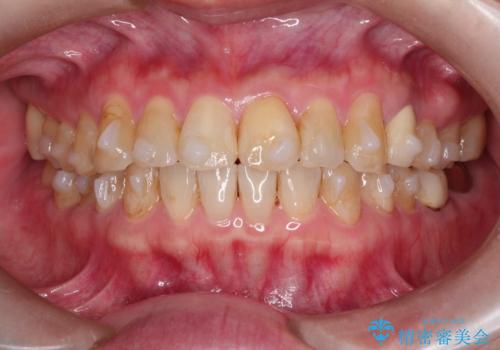

- 前歯のガタガタを主訴に来院されました。

上の歯の前突も気になってたため、奥歯の遠心移動も行いながらインビザラインにて治療を行いました。

前歯も下がり満足していただきました。

今回は奥歯の遠心移動とIPRを行って配列しています。